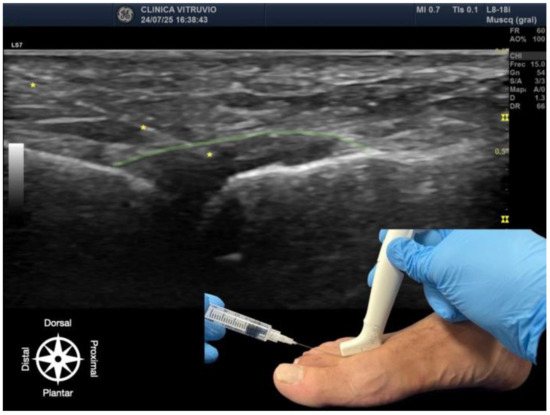

The procedure was performed using high-resolution ultrasound (10–15 MHz linear transducer) under real-time guidance (Figure 1 and Figure 2), following the selective infiltration protocol described by Ruiz Santiago et al. for Morton’s neuroma [3]. Three injections were performed on each anatomical specimen: 1—metatarsophalangeal joint of the third ray (3rd MTP joint), 2—metatarsophalangeal joint of the fourth ray (4th MTP joint), and 3—intermetatarsal space between the third and fourth rays (IM space).

Figure 2. Ultrasound-guided infiltration of the third intermetatarsal space for Morton’s neuroma. The bursa–nerve complex is highlighted in yellow, with the needle following its path, also marked with yellow asterisks (*). In the lower right corner, the plantar approach is shown, illustrating probe and needle positioning. The anatomical orientation diagram indicates the proximal–distal and dorsal–plantar axes.